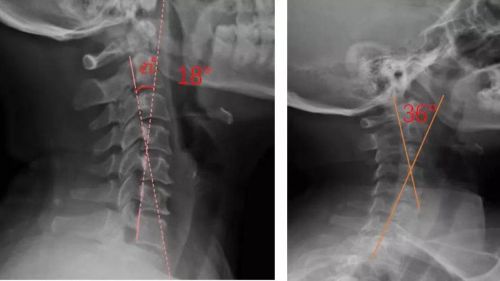

患者適配前后側位X光,佩戴前18°,適配后36°

對于頸椎病患者,合理設計的頸椎枕,能夠緊密適合頸椎,矯正頸椎生理曲度;再根據(jù)頸椎曲度改善情況,隨時間慢慢調整3D打印頸椎枕曲度,使變直的頸椎逐漸形成正常的生理曲度,改善頸肩痛的癥狀。